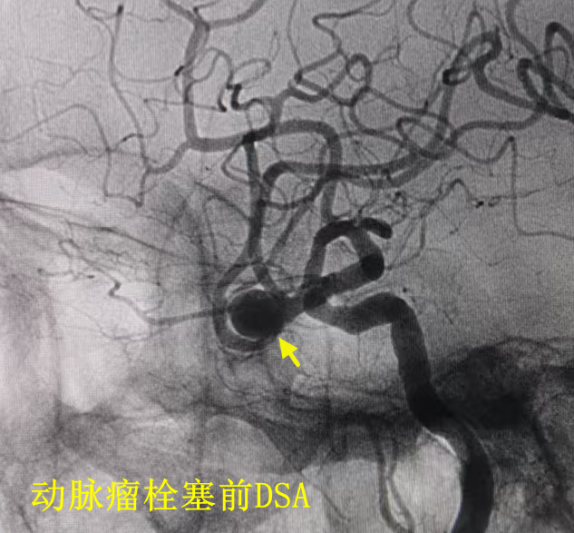

近日,面对一位古稀老人颅内破裂的“不定时炸弹”——复杂脑动脉瘤,我院神经外科团队成功应用全球前沿的自膨式动脉瘤瘤内栓塞器(WEB) ,完成了我院首例该技术下的动脉瘤精准介入治疗。 紧急救治 古稀老人突发“颅内炸弹” 71岁的张先生(化名)突发剧烈头痛伴右侧肢体乏力,经120紧急送入我院。急诊迅速启动卒中绿色通道,经头部CT及CTA检查,诊断为“广泛蛛网膜下腔出血、左侧大脑中动脉分叉部动脉瘤”。此类动脉瘤破裂风险极高,如同颅内的“不定时炸弹”,治疗刻不容缓。 术前颅脑CT见广泛蛛网膜下腔出血 CTA见左侧大脑中动脉分叉部宽颈动脉瘤 创新破局 全球新技解难题 神经外科介入团队立即组织多学科讨论,详细研判病情,制定了开颅夹闭与微创介入栓塞两套方案,家属明确选择微创手术方案。面对位于复杂分叉处且瘤颈宽大的动脉瘤,团队决定应用全球前沿的自膨式动脉瘤瘤内栓塞系统(WEB)进行治疗。在神经外科、介入中心与麻醉科的通力协作下,成功将自膨式动脉瘤瘤内栓塞系统(WEB)装置植入动脉瘤腔内,完成栓塞治疗,历经2小时。术后,造影显示动脉瘤完全隔绝,载瘤动脉通畅良好,危机解除。 技术优势 瘤内扰流新选择 自膨式动脉瘤瘤内栓塞系统(WEB)装置形似精密编织的迷你网篮,专为分叉部宽颈动脉瘤设计。相较于传统支架辅助栓塞,自膨式动脉瘤瘤内栓塞系统(WEB)技术体现了神经介入领域的重要创新: 操作简化: 单一器械即可完成治疗,流程更简洁。 安全性提升: 避免支架植入,降低了血栓等并发症风险。 患者受益: 术后无需长期服用抗血小板药物,减轻了身心及经济负担。 此例自膨式动脉瘤瘤内栓塞系统(WEB)植入术的成功开展,标志着我院在复杂脑动脉瘤微创治疗领域取得新突破,为患者提供了高效的治疗选择。作为国家卫健委能力建设和继续教育神经外科建设中心,贵州航天医院神经外科将持续依托优质资源,深化对外协作,以技术创新护航百姓健康。 神经外科专家简介 廖洪民 神经外科党支部书记、主任,主任医师 临床擅长:从事神经外科临床工作30年,对颅脑损伤、脑肿瘤、脑血管病等具有丰富诊疗经验,擅长救治重症颅脑创伤、脑出血微创治疗、脑肿瘤显微手术治疗、脑立体定向手术等。 中国医师协会神经外科分会专科认证医师、贵州省医学会神经外科分会青年委员、遵义市医学会神经外科分会常务委员、遵义市中西医结合学会脑心同治专业委员会常务委员、中国生命关怀协会脑卒中救治及康复照护专业委员会委员、贵州省脑损伤评价质控中心专家库成员、遵义市脑损伤评价医疗质量控制中心专家。 朱家伟 神经外科副主任医师 临床擅长:从事神经外科工作26年,擅长颅脑损伤救治及脑出血微创手术。 遵义市医学会神经外科分会委员、遵义市中西医结合学会脑心同治专业委员会常务委员。 黄建军 神经外科副主任医师 临床擅长:从事神经外科工作20年,对神经外科常见病、急危重症有丰富诊疗经验,熟练掌握神经外科微创手术。 神经外科科室简介 基本情况 贵州航天医院神经外科于2008年独立建科,是首批国家卫健委能力建设和继续教育神经外科建设中心,贵州省神经外科介入联盟单位。现有专业技术人员17人,其中高级职称4人,中级5人,初级7人。 科室配备STORZ神经内镜系统、德国莱卡手术显微镜,国产西山开颅动力系统、蛇牌双极电凝、Mayfield头架等颅脑手术设备,以及无创和有创颅内压监护仪、正中神经刺激仪、脑循环康复治疗仪、排痰机、下肢康复训练器、气垫床、多参数监护仪等现代化医疗设备,为病区各种急、危、重患者的观察、监护和治疗保驾护航。 专科特色 (一)脑出血微创手术治疗 应用范围:各种病因导致的自发性脑出血(高血压脑出血、脑淀粉样血管病相关脑出血、抗凝药物相关脑出血等)。 技术优势:微创、精准、恢复快。 (二)颅脑病变显微切除术 应用范围:颅内各种占位性病变(脑囊肿、脑肿瘤等)。 技术优势:精确度高、创伤小、恢复快。 (三)颅脑创伤综合救治 应用范围:各种类型的颅脑损伤、创伤性颅内血肿及颅脑创伤并发症、后遗症等。 技术优势:快速精准诊断、个体化手术与监护、早期康复干预,伤者病死率低、并发症少。